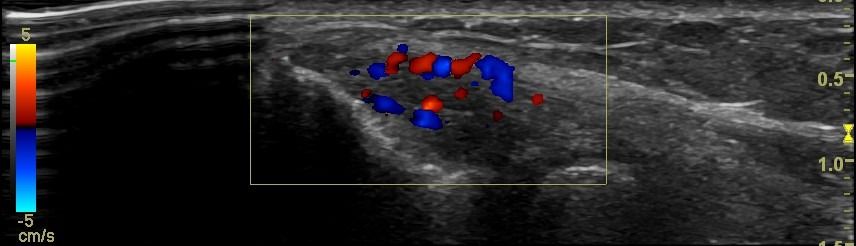

- Fluid collection in the bursa (i.e olecranon bursitis)

- Synovitis in the bursa as a symptom of Rheumatologic Disease